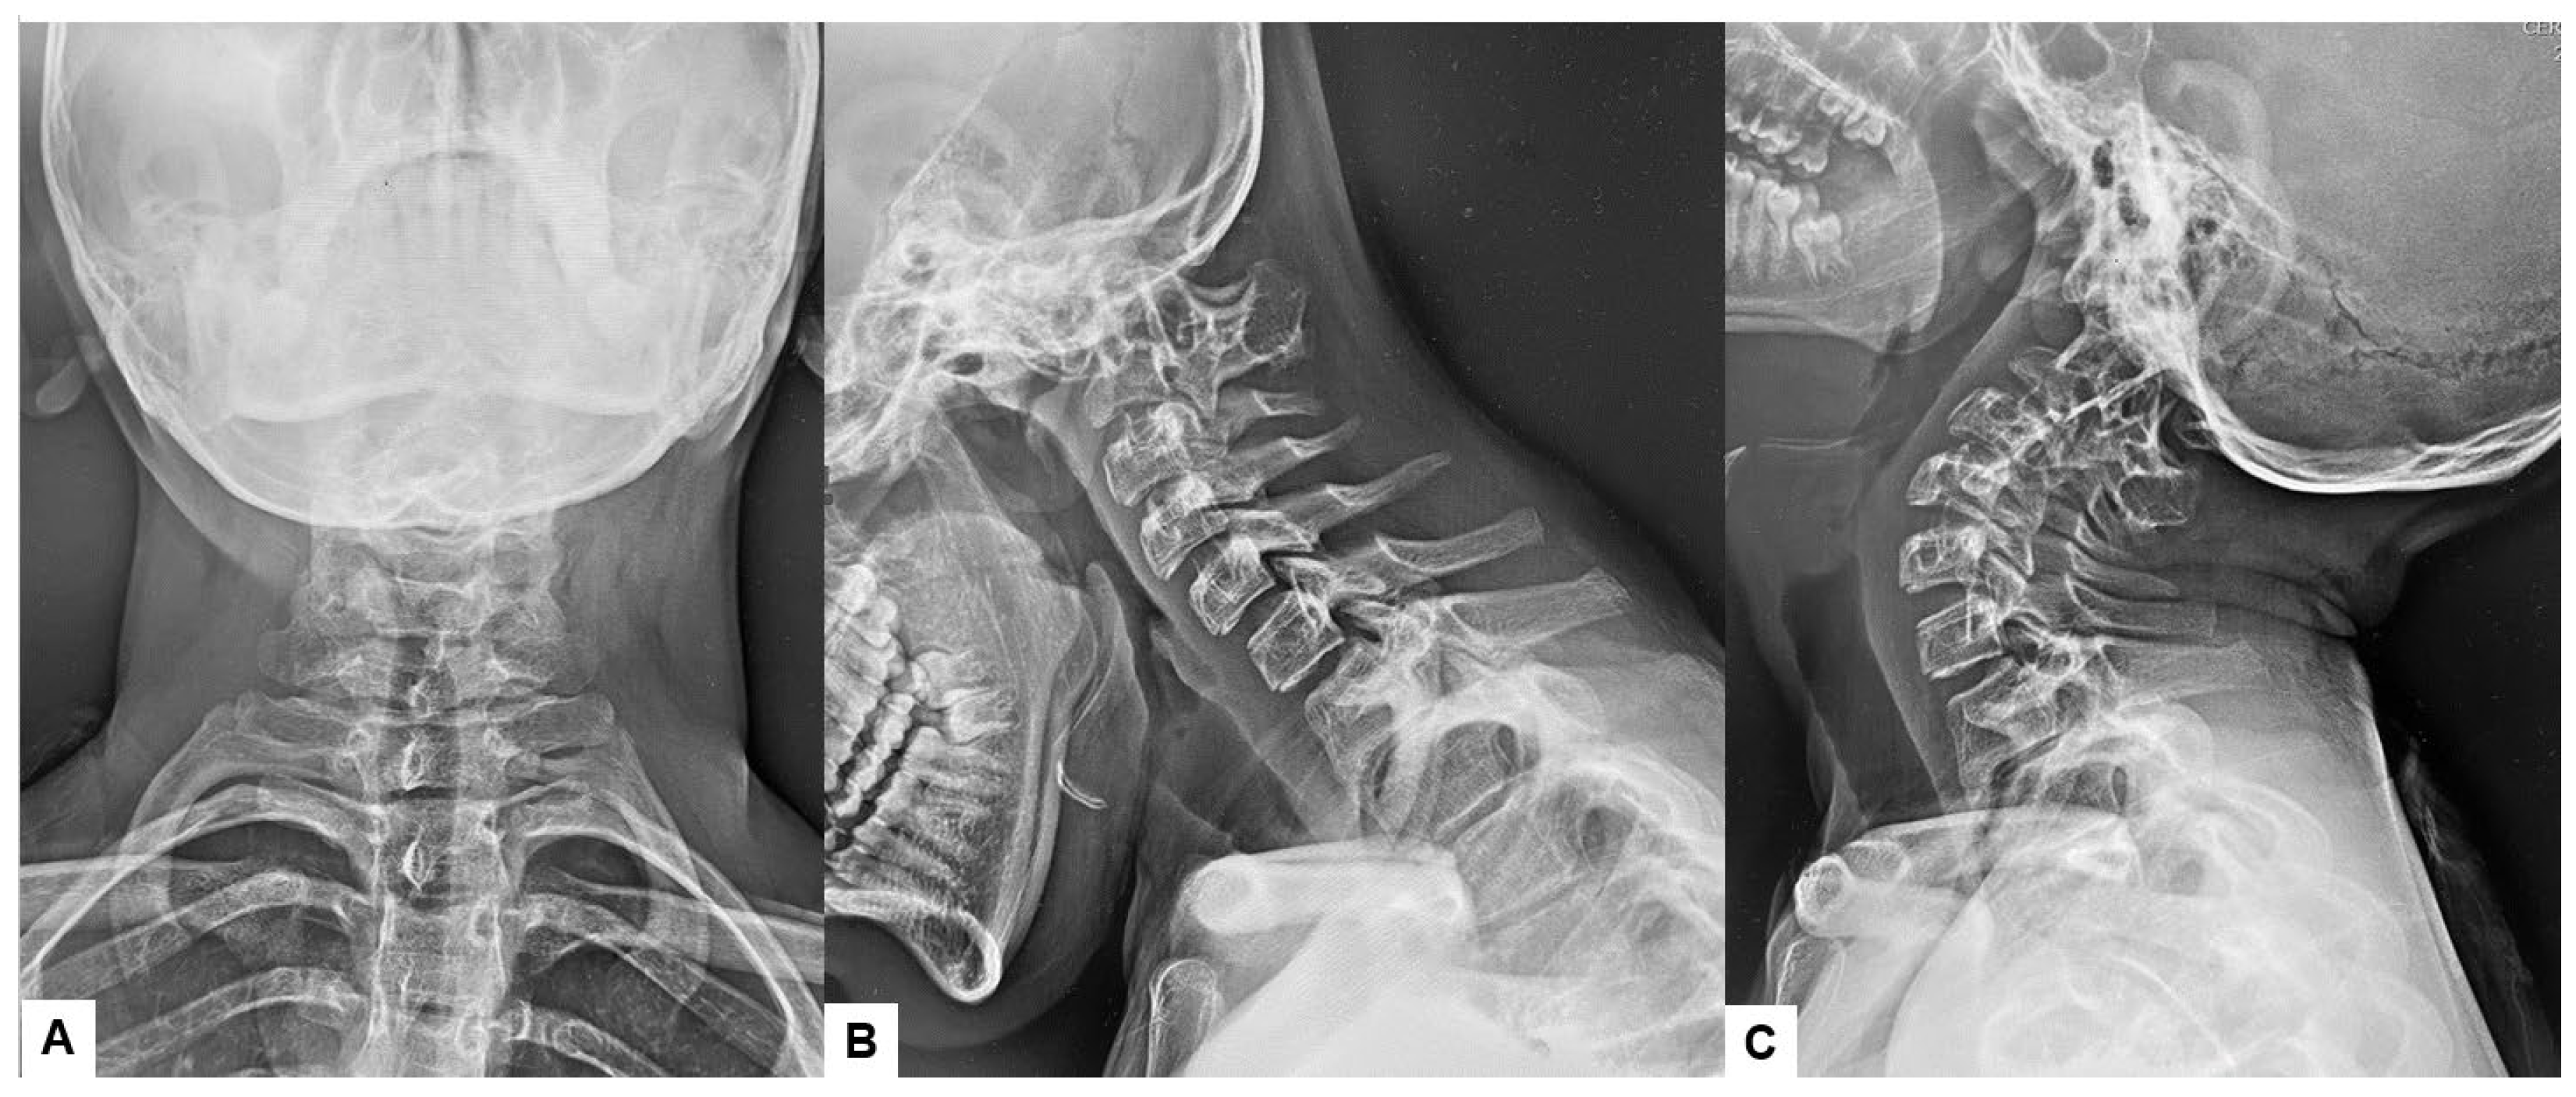

2.3. Preoperative Imaging